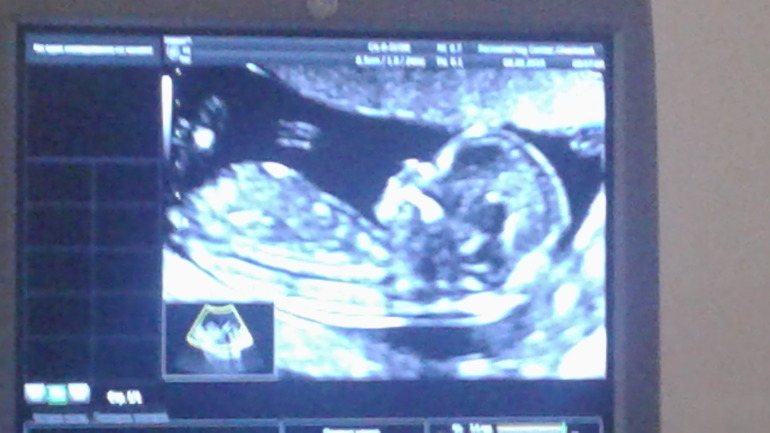

Ктр 70, твп 1,9, носик 2,4; чсс 155. Хорион по задней стенке. Всё хорошо, всё в порядке)))) Ручки закидывал за голову, ножками болтал, зевал. Крутился-вертелся))

Разрешили сфоткать экран. Такой красивый ребёнок 😆😙😊